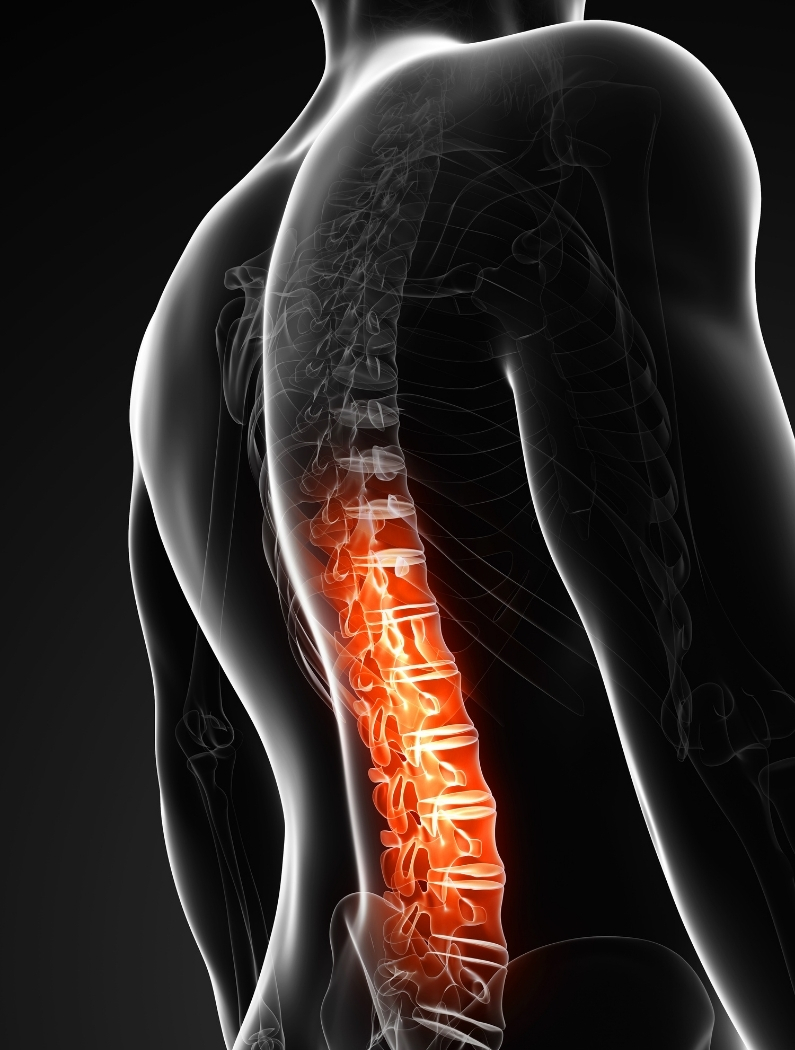

Dolor de Espalda y Lumbalgia

El dolor de espalda, especialmente en la zona lumbar, es una molestia frecuente. Puede aparecer de forma repentina o desarrollarse progresivamente, afectando actividades como caminar, sentarse, dormir o trabajar.

El dolor lumbar se localiza en la parte baja de la espalda, una zona que soporta gran parte del peso corporal y participa activamente en el movimiento, la postura y la estabilidad.

Debido a su función, esta región puede estar expuesta a:

- Sobrecargas repetitivas

- Posturas sostenidas

- Falta de movilidad

- Compensaciones musculares

Por eso, no siempre se relaciona con una lesión puntual, sino con cómo el cuerpo se ha adaptado con el tiempo.